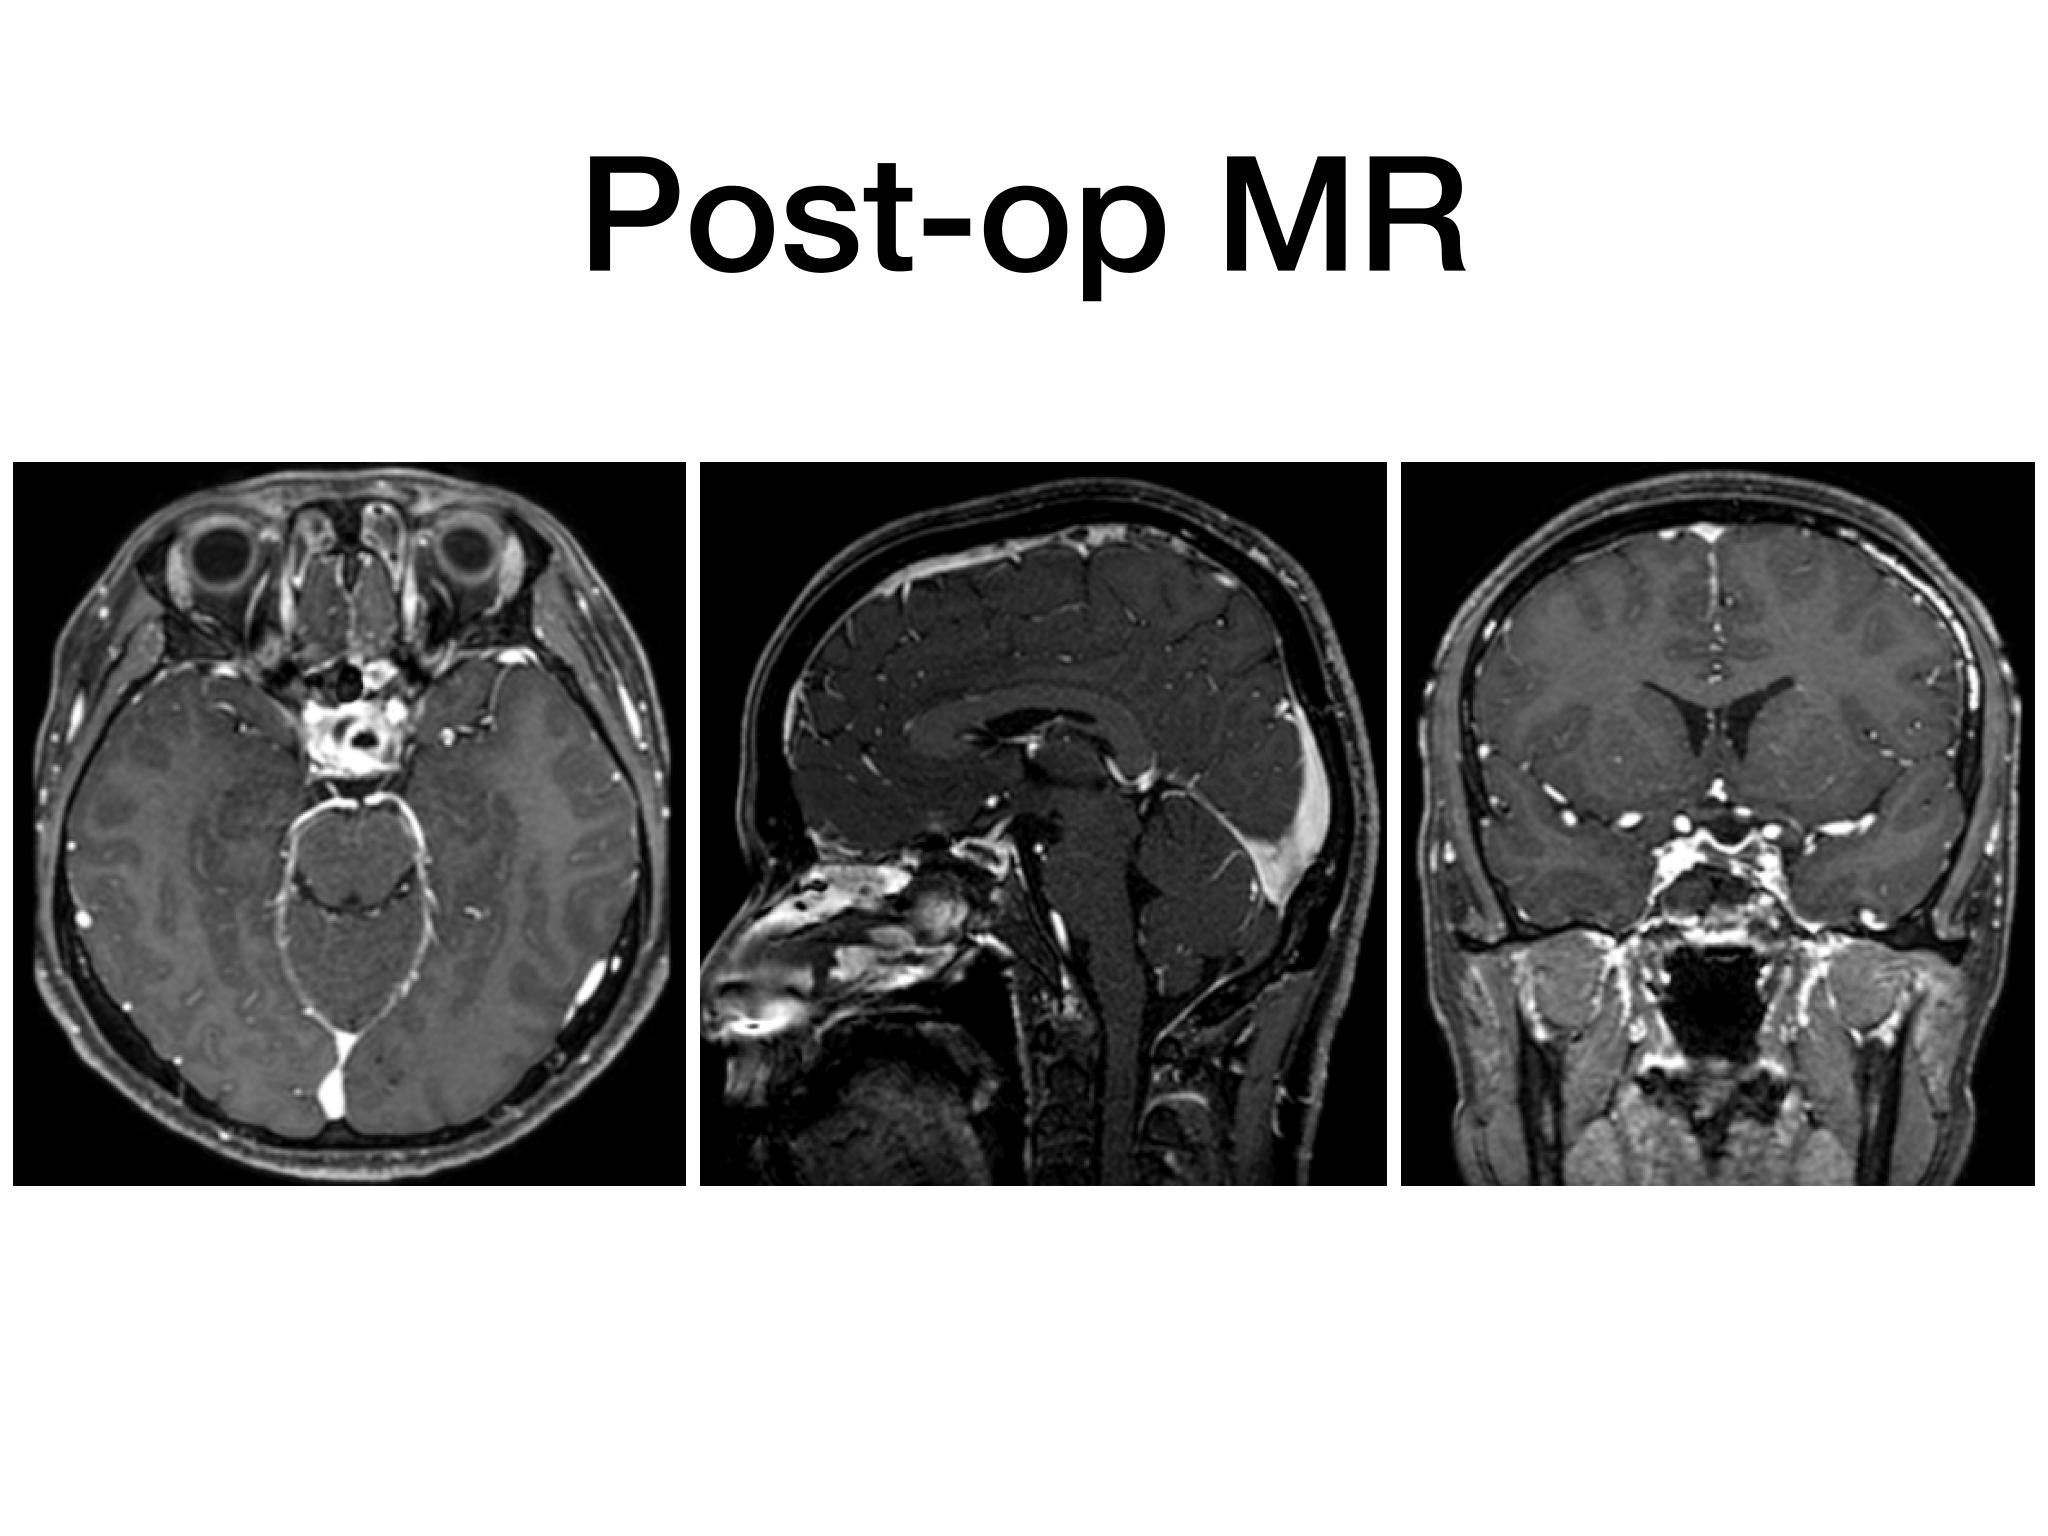

分享一例经鼻内镜泌乳素大腺瘤切除手术,患者青年男性,术前泌乳素>200ng/dl,MR提示大腺瘤合并瘤内出血,手术全切肿瘤,术后泌乳素降至正常,生化缓解,预后良好。